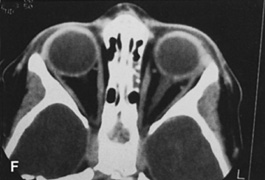

Fig. 14. A,B. Large intraorbital lymphangioma causing proptosis and optic nerve compression in a 2-year-old child. C. View of the left orbit from above after removal of the frontal bone flap, including the supraorbital rim and orbital roof. An extensive exposure of the entire superior and lateral orbit is afforded. The levator and superior rectus complex is being retracted laterally with a muscle hook, whereas the Freer elevator retracts the superior oblique muscle medially. The frontal nerve can be seen running from posterior to anterior over the superior orbit. The orbital mass is exposed in this fashion. D. The fronto-orbital bone flap is wired back in place after completion of the procedure. E. Postoperative appearance of the patient. F. The postoperative CT scan shows complete removal of the lymphangioma. This large and diffuse lesion would have been difficult to remove with any other approach.